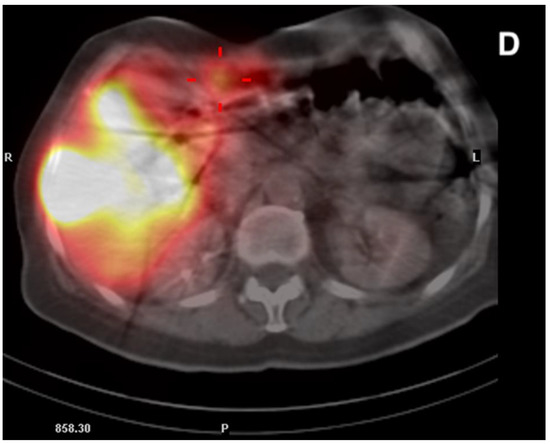

Figure 6.

(A) Angiogram of the left hepatic artery showing falciform artery travelling medially beyond the margin of the liver. (B) Its presence was confirmed on Dyna-CT and showed contrast enhancement of the abdominal wall (arrows) (C), and on SPECT/CT after 99mTc-MAA injection (D) (crosshairs).